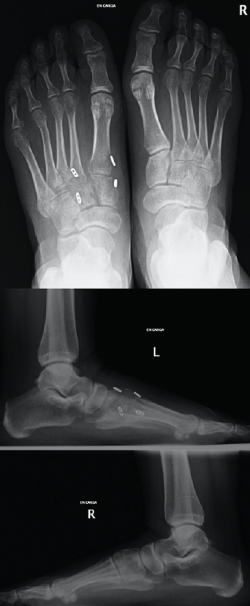

Figura 1. Caso 1. A: radiografía anteroposterior (AP) sin carga; B: radiografía oblicua sin carga; C: radiografía AP con carga con diástasis en la articulación de Lisfranc; D: radiografía lateral con carga.

Se trata de un varón de 32 años diagnosticado de lesión sutil de Lisfranc en urgencias tras un traumatismo deportivo sin especificar el mecanismo. Se realiza estudio radiográfico y tomográfico objetivando diástasis de 2 mm articular en el pie derecho sin lesión ósea (Figuras 1A y 1B). Se decide realizar tratamiento conservador con férula y descarga. Se hace una revisión a las 2 semanas, manteniendo la diástasis previa, pero en la revisión a las 6 semanas se confirma diástasis de 5 mm en la radiografía en carga, por lo que se indica tratamiento quirúrgico (Figuras 1C y 1D).